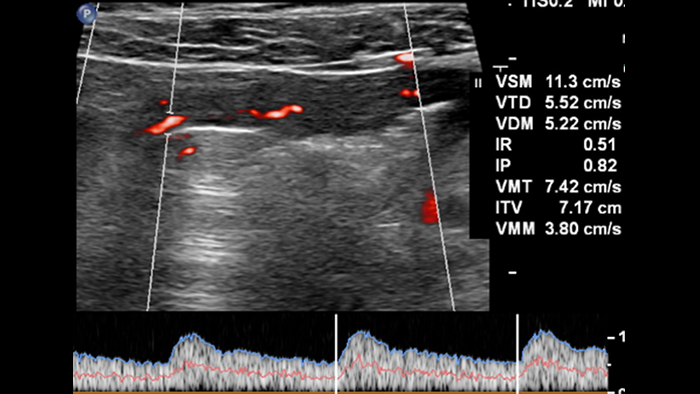

La quantification de l’inflammation est le dernier point important, mais pas le moindre, car elle intéresse le gastro-entérologue pour le suivi des patients sous traitement. L’injection d’un produit de contraste permet d’obtenir une imagerie fonctionnelle. Elle rend également la quantification possible grâce aux courbes de rehaussement en fonction du temps, qui offrent différents paramètres mesurables (niveau de pic, temps au pic du bolus, index de perfusion, etc.). Cette technique a cependant des limites réelles : elle nécessite un protocole d’injection précis (débit et quantité du produit de contraste), il s’agit d’un examen à exposition unique (une fois le produit injecté, l’exploration d’autres segments de l’intestin est impossible), et elle ne permet pas de visualiser clairement les couches touchées par l’inflammation lorsqu’elles sont masquées par les microbulles. La technologie MFI revêt donc un grand intérêt! Elle préserve la visualisation des couches de la paroi intestinale, et permet d’obtenir certains paramètres Doppler, dont la signification doit toutefois être analysée et comprise, sans se limiter à un seul segment de la paroi intestinale.

Enfin, pour utiliser la technologie MFI et définir l’activité inflammatoire de la paroi intestinale, il est nécessaire d’obtenir des images 2D optimales, d’appliquer un protocole adapté pour les paramètres de MFI afin d’assurer la reproductibilité des résultats, et d’obtenir des paramètres quantifiables. À l’avenir, pour démontrer l’intérêt de la technologie MFI dans la mesure de l’activité des maladies inflammatoires chroniques de l’intestin, il sera probablement nécessaire d’utiliser des paramètres d’imagerie protocolisés et peut-être un post-traitement des images destiné à déterminer la densité des microvaisseaux. En conclusion, cette première expérience d’exploration des maladies inflammatoires chroniques de l’intestin avec la sonde eL18-4 et la technologie MFI nous a semblé prometteuse. Bien que nous nous soyons appuyés sur la connaissance des symptômes cliniques et sur des images IRM dans la plupart des cas, nous n’avons pas recouru à une comparaison systématique avec les scores cliniques-biologiques et la pathologie de l’échantillon réséqué de l’intestin examiné. Pour valider les images des microvaisseaux, il convient toujours de mettre les images en corrélation avec les images IRM et les résultats liés à la pathologie. La comparaison systématique avec les scores inflammatoires de référence est également nécessaire pour évaluer l’intérêt de la technologie MFI à des fins de décision thérapeutique et de suivi.